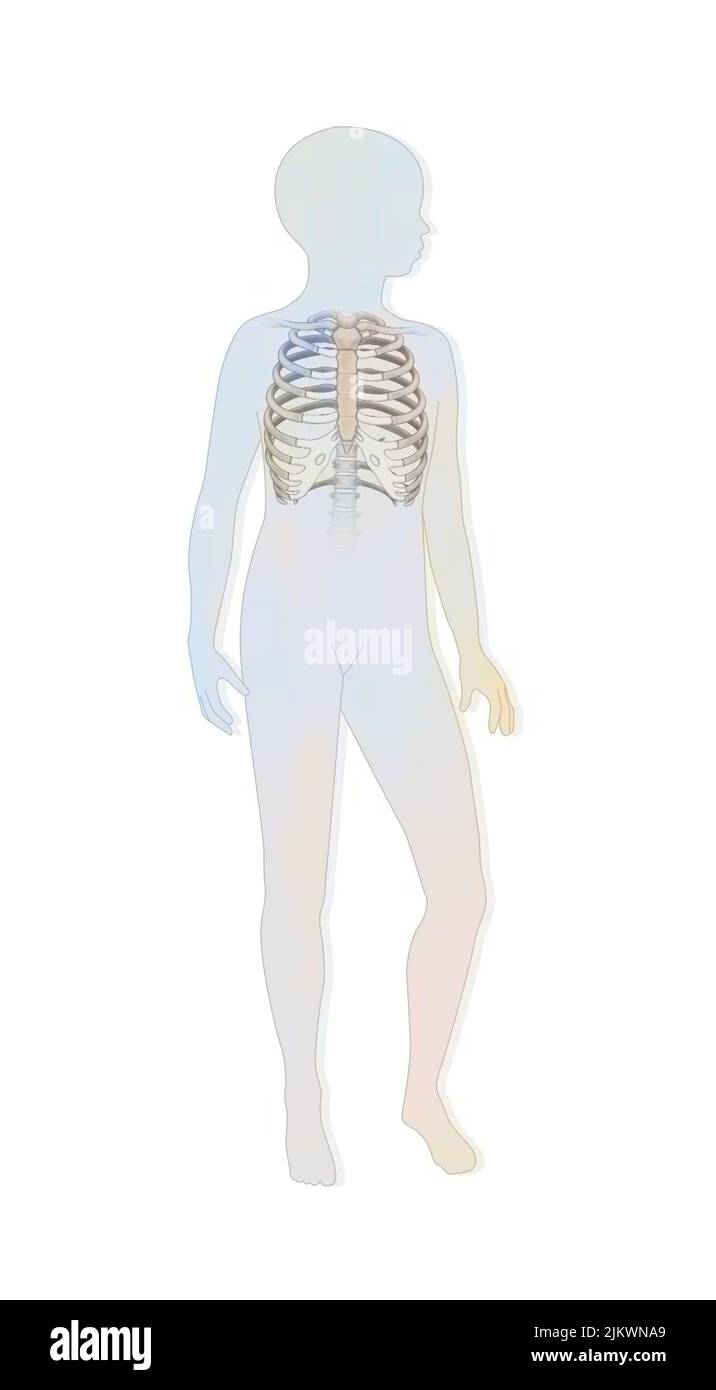

RF2JKWRMG–Thérapie génique : introduction de rétrovirus pour modifier les cellules de la moelle épinière mutées d'un nouveau-né.